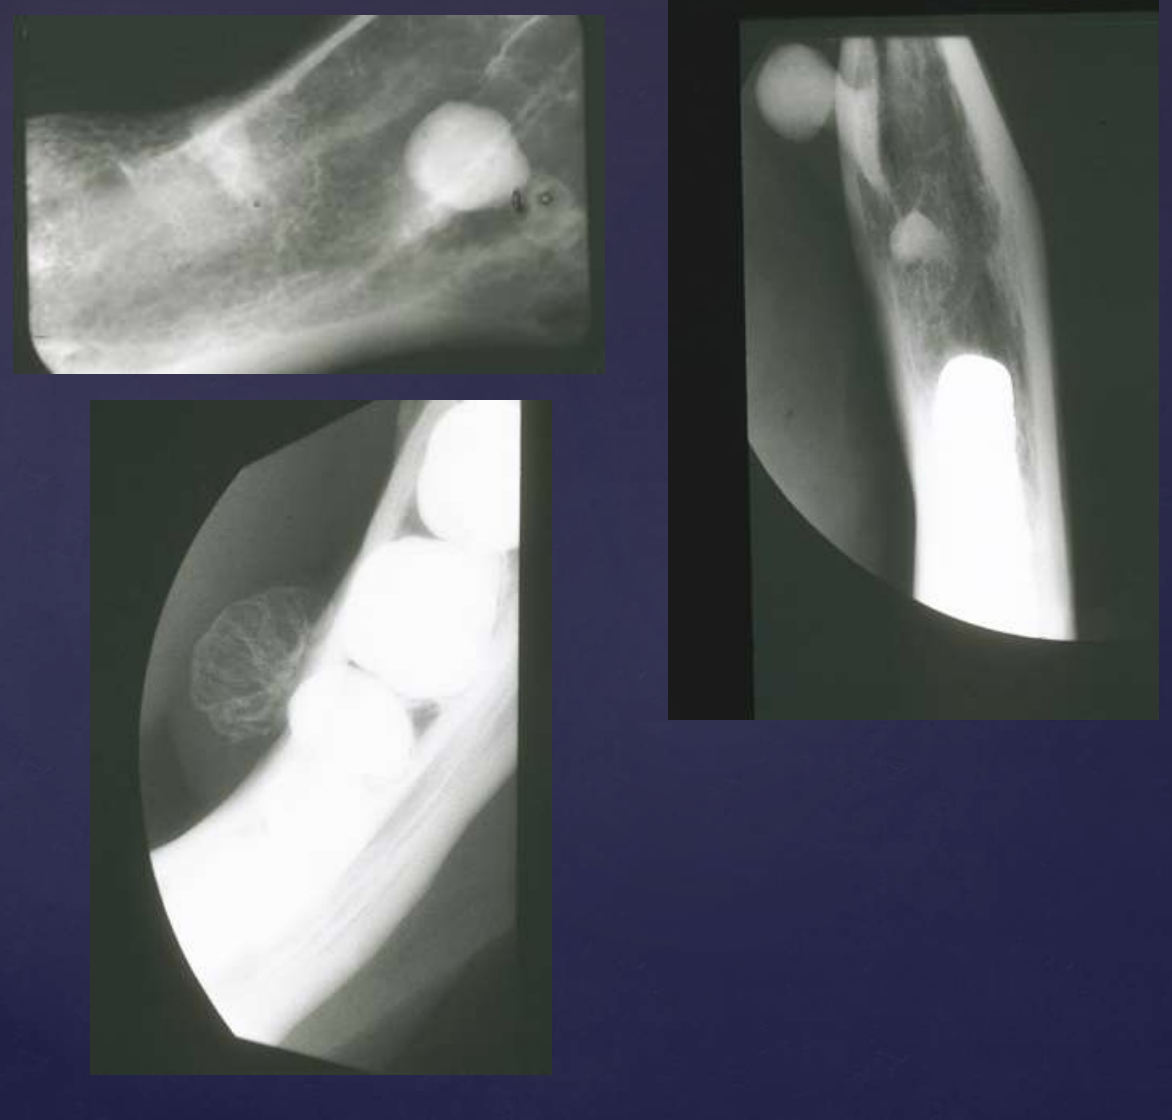

what are radiographic findings of Odontogenic Myxoma?

Variable margins

Well defined or poorly defined

Radiolucent

Multilocular

Few straight septae

Curved septae seen as well

Expansile- expands cortical margins

Tooth displacement

Odontogenic Myxoma

well-defined

multiple septum (thin, straight)

displacement of 29 root

expansion of inferior border of mandible

well defined corticated

displacement of 30, 29

external root resorption of 30

displacement of IAN canal

erosion of inferior border of mandible